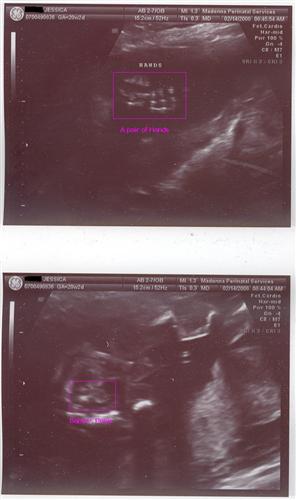

Here are a few from my 20 week sono. Fingers crossed the pictures will post... Image Attachment(s):

Aaaww I think it's cute how you can see the spine so clearly and how your baby is looking down with his/her little butt up!!!!

Here is mine. I love it!

Posted by jessbaby

See that's what i'm talking about! That's a good one compared to mine!